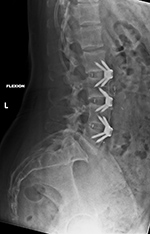

| Zero-Profile lumbar fixation L2-L5 |

| 45 year-old woman with L2-5 anterior lumbar interbody fusion (ALIF) for low back pain. The lateral views are respectively in neutral and flexion positions. The CT images are selected slices in the coronal and sagittal planes, respectively. |

| 45 year-old woman with L2-5 anterior lumbar interbody fusion (ALIF) for low back pain. |